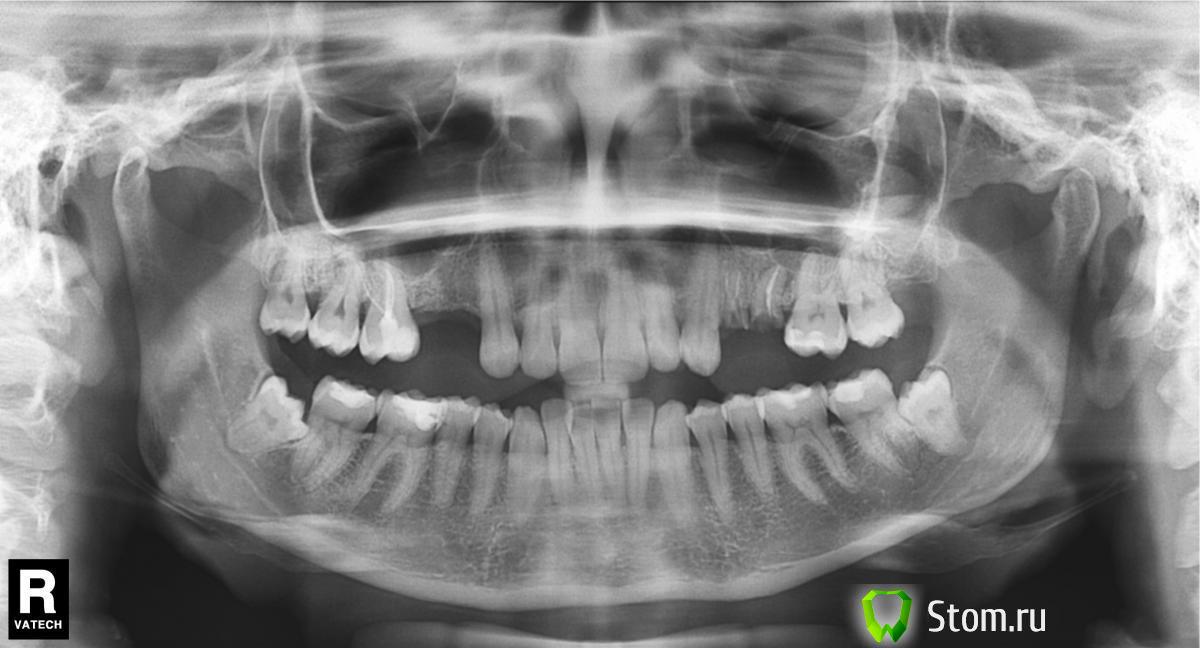

xpander Опубликовано 1 марта, 2012 Поделиться Опубликовано 1 марта, 2012 Здравствуйте.Помогите найти хорошего специалиста\команду в Москве с комплексной консультацией и лечением. Под словом команда я подразумеваю какую-то совместную консультацию со специалистами и принятие коллегиального решения в лечении.Насколько я понимаю у меня запущенный случай: неправильно растут зубы мудрости, с прикусом плохо, в течении 5 лет обещают рецессию десен, куча кариеса и вообще...Есть томография: tomografy.zip пароль:q1w2e3 (хостинг народ.ру 48.8мб morita) Ссылка на комментарий